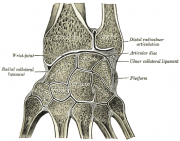

| 2021年7月26日 (一) 18:31 | Gray336.png (文件) |  |

48 KB | 77921020 | Uploaded with SimpleBatchUpload | 1 |